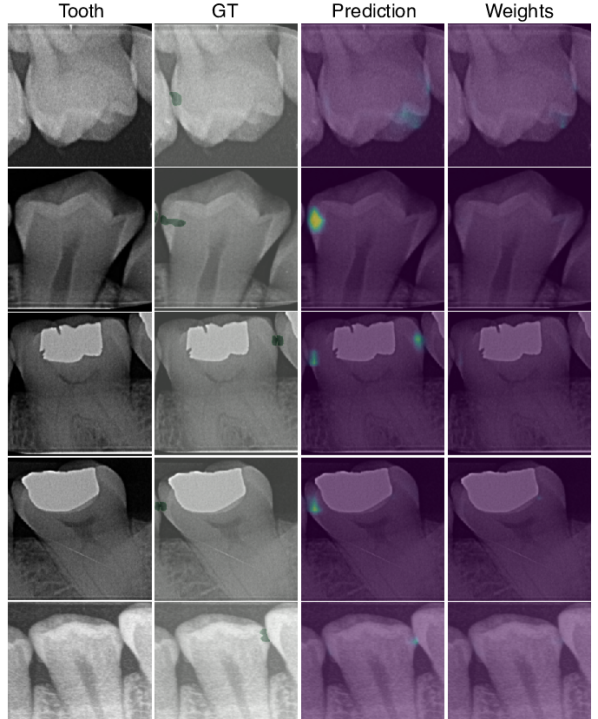

fig:tooth_kernel

The second hyperparameter is the patch size, which we set equal for both dimensions, – we use in the following to denote both width and height. The patch size controls the individual regions that are classified. If , then a single global patch is considered and the training behavior is similar to a standard CNN. Fig. LABEL:fig:tooth_kernel shows the effect of on the heatmap for . Attention weights of overlapping patches are summed and clipped at 1 to improve visualizations. One can observe that the sensitivity increases while precision decreases. In our experiments, the patch size had little impact on classification performance, but we prefer a small value for precise localization. Note that a small patch in the embedding space has a large receptive field and thus sufficient context to detect both small and larger lesions Luo et al. (2016). For the main experiments, we set , and .